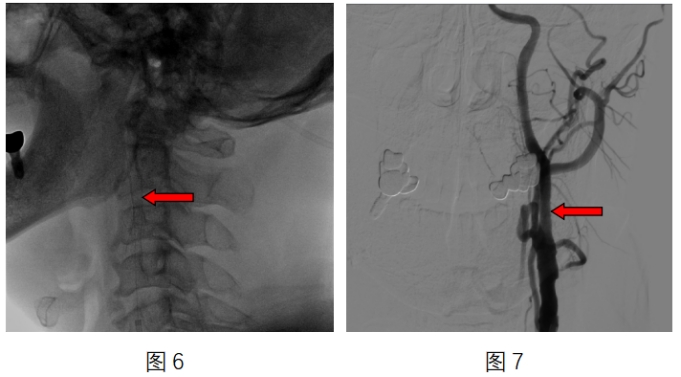

图6介入手术置入的支架

图7术后颈内动脉狭窄处恢复正常管径